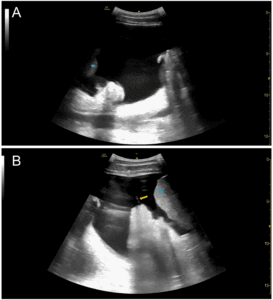

The ultrasound probe should initially be placed in the mid-axillary line at the level of the xiphoid process with the indicator towards the patient’s head. The diaphragm should be visualized along with the liver in position 1 and the spleen in position 4 (Figure 1).  In addition, the kidneys and thoracic spine should be identified in the abdomen. This usually requires sliding up and down between ribs spaces, sweeping the probe posteriorly, and tilting in the anterior-posterior plane. The thoracic spine can be identified because ultrasound waves reflect of bone, creating the hyperechoic appearance of the vertebral bodies with anechoic shadows deep to them. With the probe in the mid-axillary line, the vertebral column can be identified at the bottom of the screen. Normal aerated lung does not provide an acoustic window to visualize any deeper structures, thus the spine is only seen when there is pathology at the lung base, such as a pleural effusion. Visualization of the thoracic spine above the diaphragm is referred to as the “spine sign,” which confirms that pathology (such as pleural effusion) is not an artifact. The absence of a pleural effusion is often noted by a positive “lung curtain sign,” in which pleural sliding and A-lines are seen at the lung base during inspiration [12].  When present, a pleural effusion is anechoic (black) and if large enough will lead to atelectasis of the nearby lung (Figure 2, Supplementary Video 1, 2).  Loculations can be present in highly exudative pleural fluid. It is important to identify the thoracic spine posterior to pleural effusions (positive “spine sign”) to rule out artifact [13].  Rib artifacts and reflection across the diaphragm can lead to hypoechoic and anechoic findings above the diaphragm, but these will not have a positive spine sign.

Figure 2: Sample FASC Examination images. FASC position 1: right pleural effusion. FASC position 2: right lower abdominal ascites. FASC position 3: a pericardial effusion. FASC position 4: a left pleural effusion. FASC position 5: lower abdominal quadrant ascites. FASC position 6: pelvic ascites around the bladder. White arrows indicate anechoic fluid collections.

In the supine position, ascites collects in the dependent locations, such as the sub-diaphragmatic space (Figure 2).  Sliding the probe inferiorly from the diaphragm level when in position 1 and 4 allows for identification of the hepatorenal recess (Morrison’s pouch) and splenorenal recess, respectively. This fluid will be detected by its anechoic (black) appearance on ultrasound and requires correct identification of nearby structures.  A fluid filled stomach, loops of bowel, or renal cysts can mimic ascites.